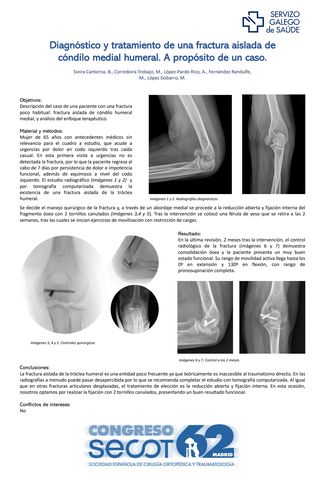

Diagnóstico y tratamiento de una fractura aislada de cóndilo medial humeral. A propósito de un caso.

BLANCA SIEIRA CANTORNA, MARTA CORREDOIRA TROBAJO, ALEJANDRO LÓPEZ-PARDO RICO, MARCOS FERNÁNDEZ RANDULFE, MARTA LÓPEZ DOBARRO